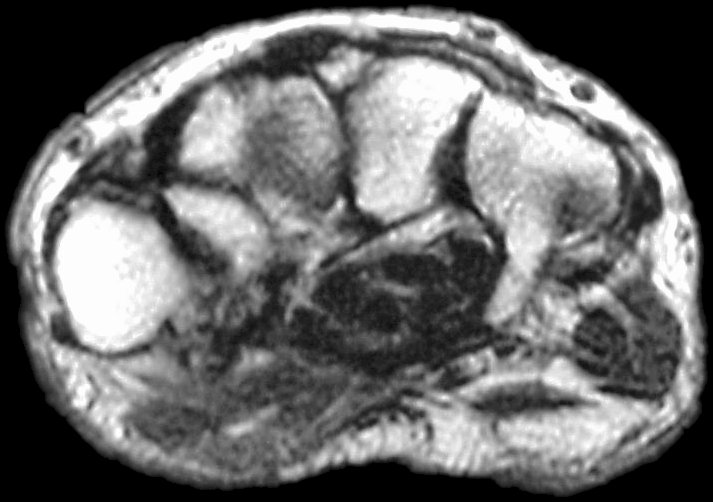

Sections through the carpal tunnel -  looking for a hook of hamate fracture or tendon discontinuity - were read as normal, although there may be a subtle signal irregularity through the hook of the hamate:

Is that a tendon rupture adjacent to the pisotriquetral joint?

The diagnosis was flexor tendon rupture, site uncertain. He was explored and found to have ruptured both flexors of the small finger within the carpal tunnel: